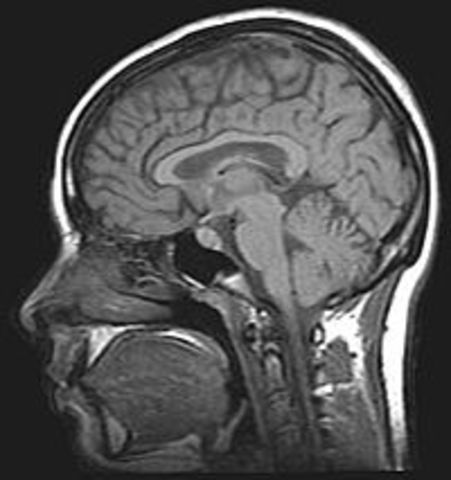

• Resonancia Magnética

Resonancia Magnética

Premio Nobel de Medicina a Paul Lauterbur y a Peter Mansfield por sus descubrimientos sobre la Resonancia Magnética -resonancia de los átomos de hidrógeno cuando son bombardeados con ondas electromagnéticas desde un imán- y su aplicación en la obtención de imágenes médicas.